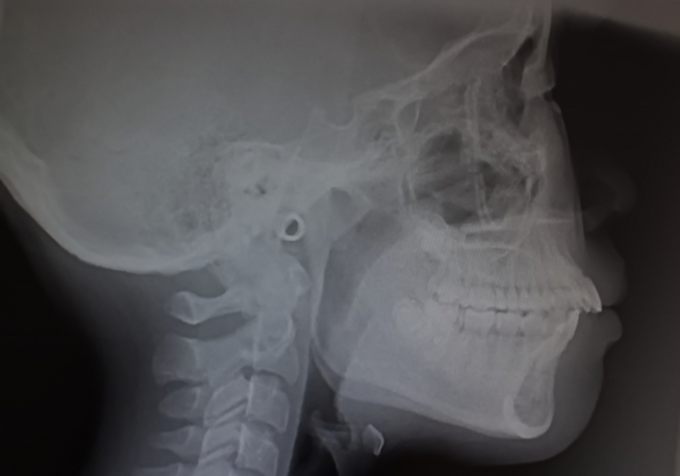

CT・セファロによる骨格診断

矯正治療において、正確な骨格診断は治療に欠かせません。当院では、CTスキャンとセファロ(頭部X線規格写真)を用いて、患者さまの骨格や歯の位置関係を詳細に分析します。em>CTスキャンは歯や骨の立体的な画像を提供し、骨の構造や形態を正確に把握できます。一方、セファロは顔面の骨の角度や歯の配列を計測し、矯正治療における骨格のズレを把握します。これらのデータをもとに、最適な治療計画を立案し、より精度の高い矯正を実現します。